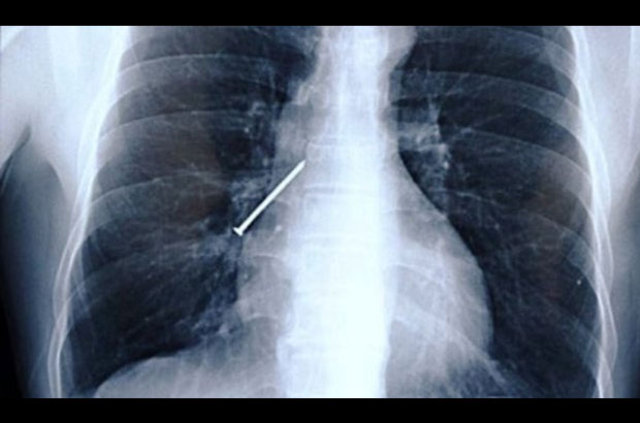

Cumhuriyet Üniversitesi (CÜ) Tıp Fakültesi Araştırma ve Uygulama Hastanesi Göğüs Cerrahisi Anabilim Dalı Servisi'nde insanların yanlışlıkla yuttuğu cisimlerden oluşturulan koleksiyon, görenleri hayrete düşürüyor.

Operasyonla mideden ya da nefes borusundan çıkan parçalar zaman zaman hekimleri bile şaşırtıyor.

Aralarında iğne, metal kolye, vida, protez diş, dikiş iğnesi, kemik parçası, pisi pisi otu, çivi ve akasya dikeni de bulunan cisimleri koleksiyon yapan hekimler, vatandaşların ağızlarına aldıkları şeylere dikkat etmeleri gerektiğini dile getiriyor.

Prof. Dr. Ekber Şahin, AA muhabirine yaptığı açıklamada, Sivas'ta son yıllarda yetişkinler ve çocukların yuttuğu yaklaşık 700 civarında yabancı cismi insanların mideleri ve nefes borularından başarıyla çıkardıklarını söyledi.

Operasyonlarda yabancı cisimlerle karşılaştıklarını ve şaşırdıklarını anlatan Şahin, "Çıkardığımız bu cisimlerin bir kısmıyla koleksiyon oluşturduk. Yıllardır çıkardıklarımız biriktirdiklerimizin 20-30 katı kadar" dedi.

Çıkardıkları cisimler arasında iğneler, metal kolyeler, vidalar, protez dişler, dikiş iğneleri, kemik parçaları, pisi pisi otları, çiviler ve akasya dikeni bulunduğunu kaydeden Şahin, "Bir insan akasya dikenini nasıl yutabilir diye çok şaşırıyoruz.

Bunları insanların soluk borusundan çıkartıyoruz. Bunlar bizim çıkardıklarımız. Daha değişik yabancı cisimler yutup hastaneye ulaşamayan hastalarımız da var.

Bize gelenler şanslı olanlar, daha kötü neticelere yol açmadan, müdahalemiz sonunda hayatta kalabilenler" diye konuştu.